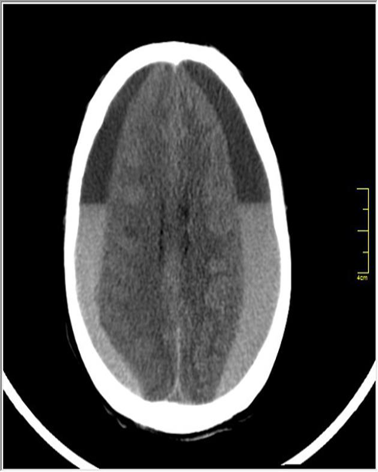

Acute subdural hemorrhage - CT head (without IV contrast; axial section; brain window)

There is a large, crescent-shaped, hypodense lesion over the lateral aspect of the left hemisphere. Mass effect of the lesion is visible as compression of the left lateral ventricle. These findings are characteristic of a large chronic subdural hematoma.